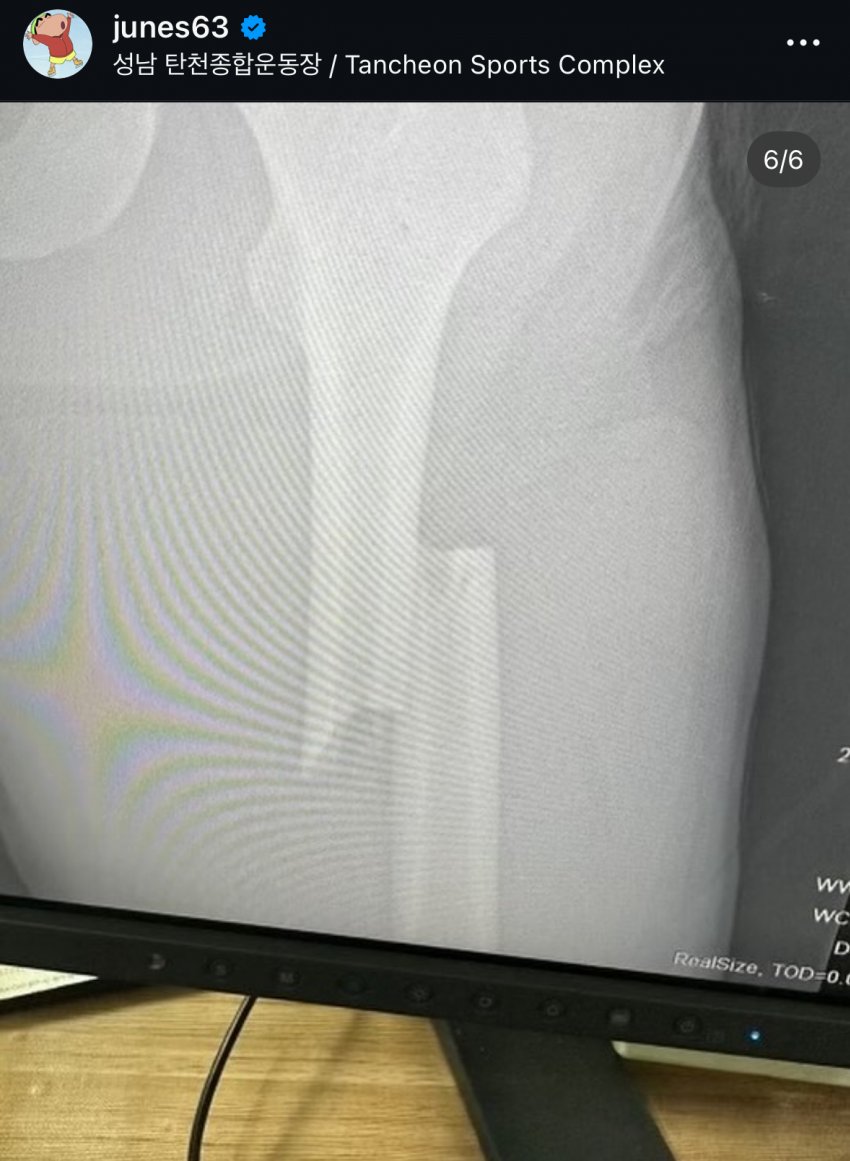

와 쇼트 계주 이준서 상태가 이랬었대...

연습 중에 허벅지 뼈 아예 나갔었나봐...

그러고 이번에 극복해서 올림픽 나왔나봄

대퇴골에 철심 박고 계주멤 단 것도 기적인 상황임